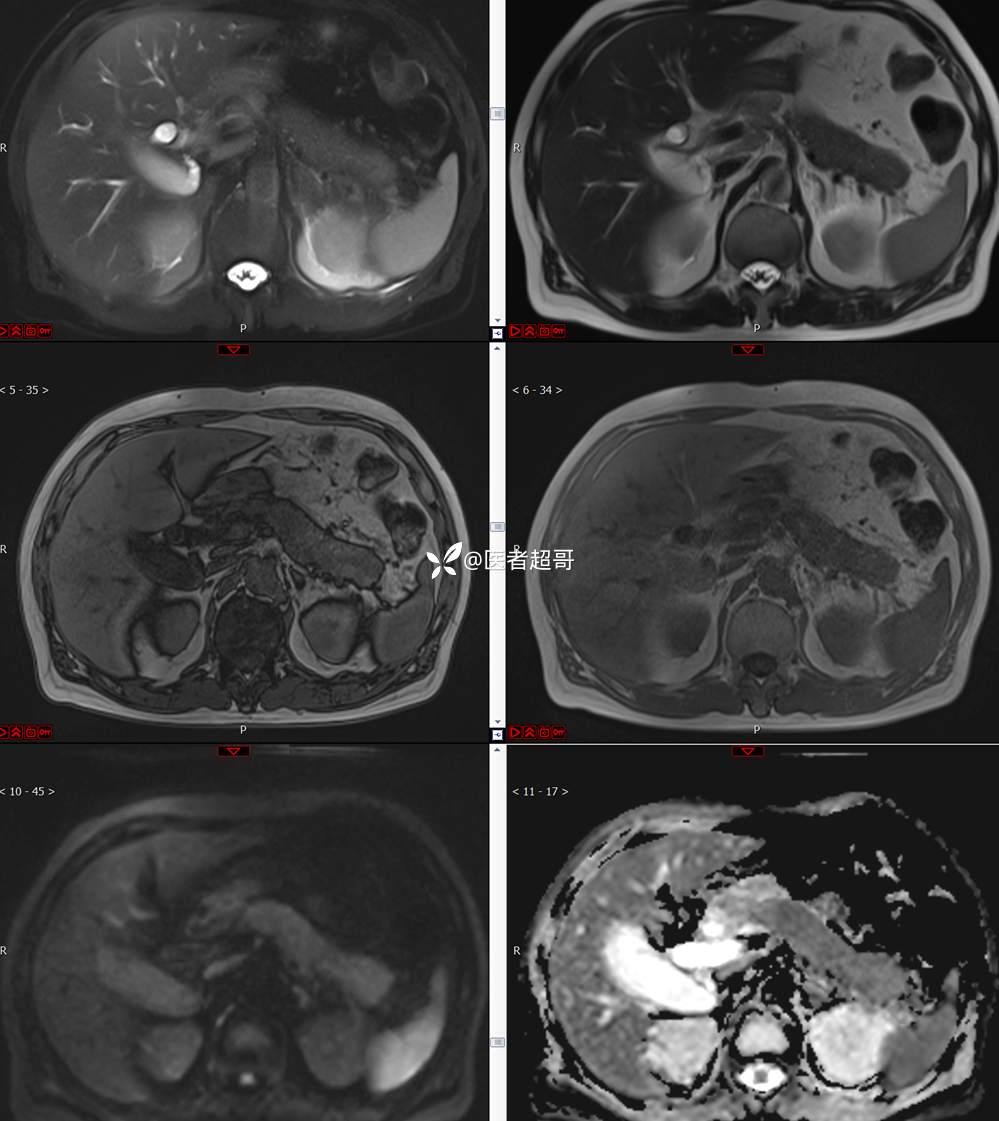

【影诊笔记772】腹痛就诊,发现肾脏病变,CT、MRI齐全,请高诊!

男,63岁 0200825 01

主 诉:间断腹痛15天

现病史:患者15天前无明显原因及诱因出现腹部疼痛不适,呈间断性钝痛,右下腹为著,无尿频、尿急、尿不尽,无发热、寒战,无腹胀。于市中心卫生院住院治疗,超声示:胰头低回声包块,胆系扩张,左肾囊肿,胆囊壁毛糙,胆囊内胆汁淤积。患者为求进一步诊治,遂以“肾盂肿瘤”收入院,患者自发病以来,神志清,精神可,饮食睡眠可,大便无明显异常,近期体重无明显增减。

既往史:既往体健